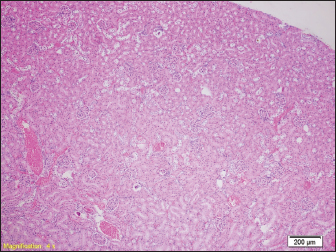

Fig. 6. Congested portal blood vessels as well as sinusoids, and hepatocytes with balloon appearance in places (HE, ×200).

Signs of degenerative changes caused by drowning were found in the liver samples. It is believed that drowning and hypotension during recovery lead to irreversible changes in the organs caused by a lack of oxygen. Similar changes were found in other studies, where the liver showed small but numerous clusters of hyaline bodies in the liver sinusoids (Ikeda et al., 1998).

Our results show signs of overcrowding of hepatic sinusoids with partially ballooned hepatocytes. These results were found in previous studies, where hepatocytes had hydropic degeneration (Ibrahim et al., 2022). The changes that can occur to the organs can largely depend on the type of water in which the drowning occurred, from salt water to fresh water. In our study, rats were drowned in water from the Bosnia River. Upon examination of the heart muscle, we found congested blood vessels, with no signs of degeneration. In contrast to our results, Mahrous et al., found signs of cardiac muscle cell damage after drowning in salt water, which were presented as a greater number of vacuoles in the cytoplasm, a reduced number of nuclei in the cells, and an inflammatory infiltrate, but also edema and congestion of blood vessels as in our results (Ibrahim et al., 2022). Christe et al. (2008) found an enlarged heart on the post-autopsy material, with an increased volume of the right atrium and right ventricle, while the left side of the heart was enlarged in only one person (Christe et al., 2008).

However, studies have shown that there are statistical differences in the number of diatoms in false positive cases and actual drowning cases. Therefore, a comprehensive analysis of multiple organs, rather than just one organ, would be more useful for the diagnosis of drowning. Relatively uniform changes are observed in the liver samples of all groups of rats, which in each sample include a certain degree of congestion, with overcrowding of the centrolobular veins, but also the veins of the portal space, as well as dilation of sinusoids-filled with erythrocytes, while hepatocytes in places show signs of paper degeneration.